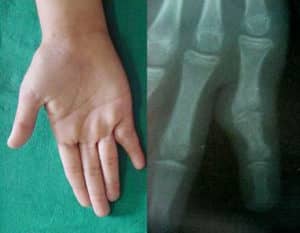

Un signo característico por el cual se puede sospechar el desarrollo de anquilosis es una articulación deformada e inmóvil. A menudo, la deformidad se desarrolla en una posición antinatural, «desfavorable» para el paciente. Cuando intenta mover la articulación, hay una pérdida completa de funcionalidad.

En las etapas iniciales, se observa rigidez en la articulación, acompañada de dolor e hinchazón. Gradualmente, la articulación deja de moverse y la extremidad o los dedos se congelan en la posición en la que aparecieron los primeros signos de fusión.

Con anquilosis ósea, la articulación es indolora. La proliferación de tejido conectivo se acompaña de dolor si la articulación puede realizar movimientos de balanceo. Una ligera hinchazón acompaña el proceso. Si el proceso inflamatorio continúa en la articulación, pueden persistir los síntomas característicos de la enfermedad que condujo a la anquilosis.

Reconocer la patología es fácil. Al examinar la articulación afectada, hay un cambio en la forma de la bolsa articular y una falta total de movimiento. De los métodos de hardware, se prescribe la radiografía o la tomografía computarizada, que le permitirán examinar en detalle los cambios degenerativos en la articulación.